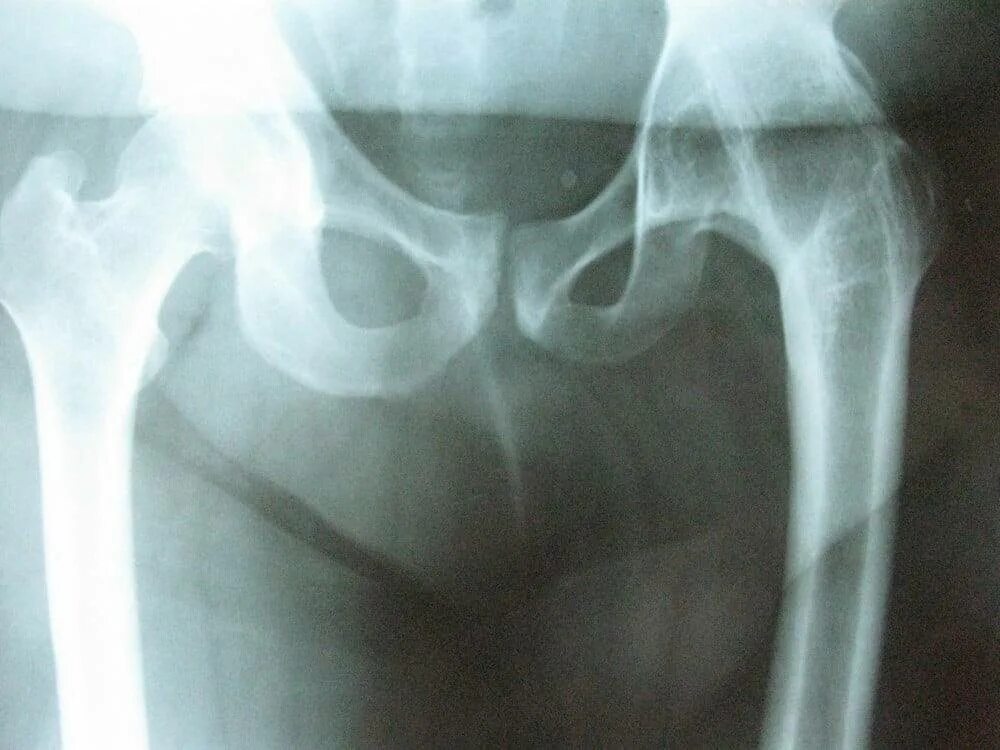

Артроз тазобедренного сустава без операции